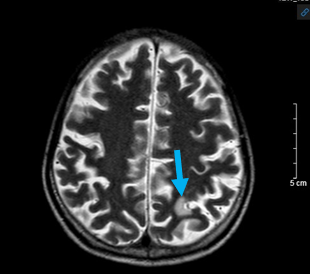

-Hình ảnh chụp cộng hưởng từ sọ não (15/03/2024):

Hình 6: Hình ảnh chụp cộng hưởng từ sọ não: Tổn thương giảm tín hiệu trên xung T1 tiêm thuốc (mũi tên đỏ) và tăng tín hiệu trên xung T2 và Flair (mũi tên xanh) tại vị trí ranh giới chất trắng -  chất xám vị trí thùy đỉnh trái – chưa loại trừ tổn thương thứ phát (bệnh nhân không có tiền sử đột quỵ não ).

Kết luận: Hình ảnh ổ tổn thương ranh giới chất trắng – xám thùy đỉnh trái – chưa loại trừ tổn thương di căn.